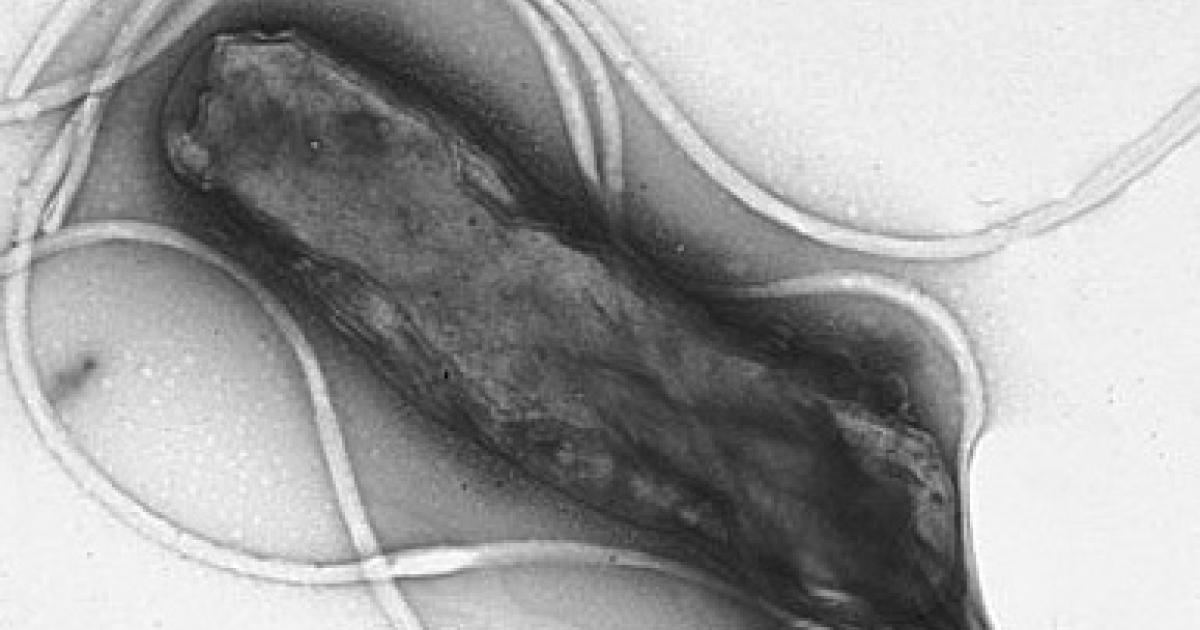

Helicobacter pylori. H. pylori gained notoriety when it was shown to be the actual cause of ulcers, not stress and poor diet as was previously believed. (Incidentally, the link between H. pylori and ulcers was conclusively demonstrated in one of the craziest self-experiments ever: Barry Marshall, an Australian doctor, isolated the bacterium from a patient with gastritis and drank it. He then developed gastritis, a precursor to an ulcer.) H. pylori is also known to cause stomach cancer. But since it's a bacterium, it's susceptible to several different antibiotics.